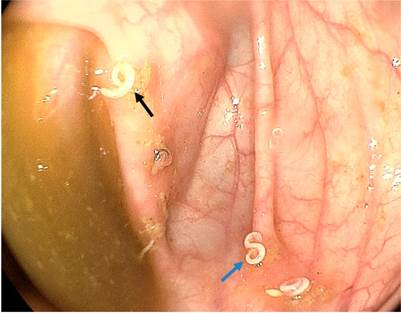

Después de leer el artículo de Pizza y colaboradores 1 sobre el diagnóstico endoscópico de la uncinariasis, considero importante mencionar algunos aspectos relacionados con dicho proceso diagnóstico, ejercido en un paciente con anemia. Este paciente fue llevado a estudios endoscópicos y se le identificó un parásito móvil en el duodeno, así como múltiples vermes en el colon ascendente y en el ciego. Se asumió entonces que los hallazgos presentes en la esofagogastroduodenoscopia y en la colonoscopia eran compatibles con la uncinariasis.

Sin embargo, los helmintos pertenecientes a los géneros Necator americanus y Ancylostoma duodenale se alojan en las porciones superiores del intestino delgado, mientras que los del género Trichuris trichiura residen dentro del ciego y el colon ascendente 2. En el caso descrito por este artículo, debe considerarse que los agentes etiológicos identificados, tanto en la endoscopia como en la colonoscopia, son de diferente especie, si se tienen presentes los sitios de hábitat usual de dichos gérmenes, así como los aspectos macroscópicos claramente evidenciados en las dos fotografías anexas.

En ellas se observa un gusano con un extremo enrollado en el ciego, que semeja las características macroscópicas del T. trichiura macho 2,3) y con un aspecto distinto al verme detectado en la endoscopia alta. Del mismo modo, el T. trichiura puede configurar particularidades clínicas semejantes a la infección por uncinarias, como anemia severa, e incluso es posible que se presente un cuadro de disentería por T. trichiura3,4.